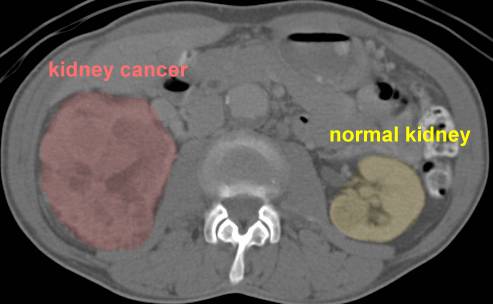

cancer images:

CT/MRI: